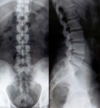

- Radiographie du rachis lombaire : profil et de face